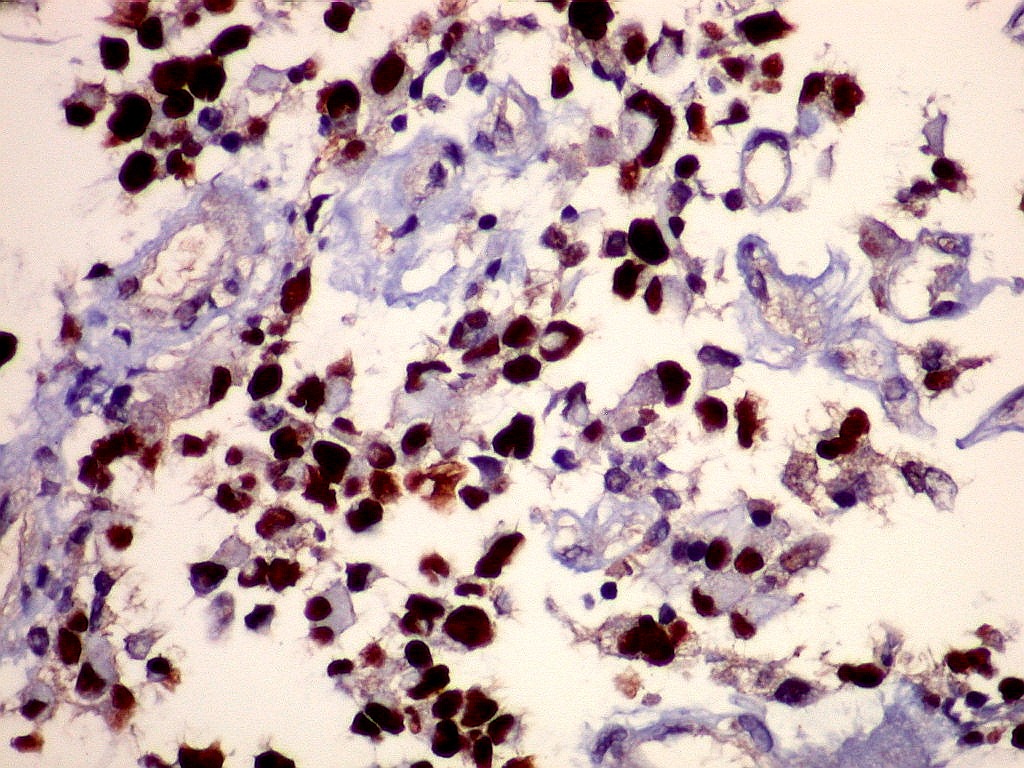

p53.      Positivo na virtual totalidade das células neoplásicas.  Indica mutação do gene p53, impedindo a apoptose das células com genoma incompatível com a normalidade.  Isto é notado apenas nas células neoplásicas.  Células vasculares e linfóides não marcam, pois não pertencem ao tumor, sendo derivadas dos tecidos hospedeiros.